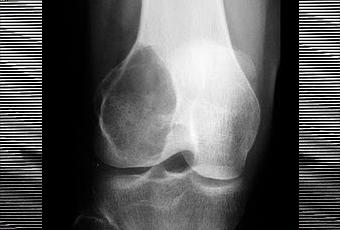

Tumeur osseuse à cellules géantes - au niveau du genou